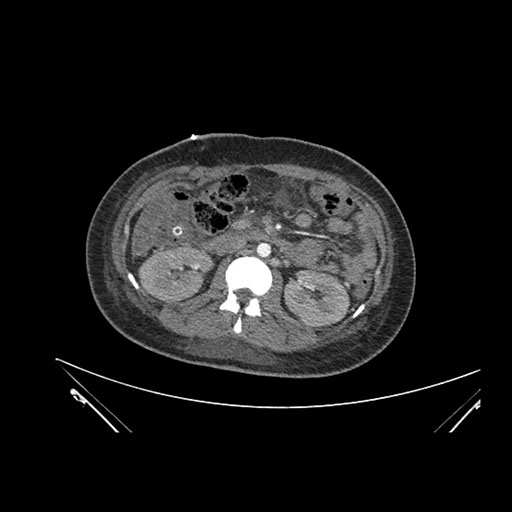

Vasculobiliary injury [M28]

Imaging Analysis

Look through the patient's CT scan to identify any areas of concern for the necessary procedure.

Axial Venous